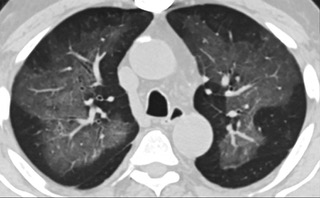

疑點一,電子煙患者的CT影像和臨床表現(xiàn)并不具有特異性。所謂美國電子肺炎患者,其實是對沒有其他合理診斷證據(jù)、吸食電子煙肺炎患者的統(tǒng)稱。這些患者在病發(fā)前90天內(nèi)吸食了電子煙,尤其值得注意的是,部分患者的CT影像特征和臨床表現(xiàn)與病毒性肺炎患者極其相似。

中、下肺軸位CT平掃顯示毛玻璃樣混濁伴胸膜下保留。(同一病人CT影像)